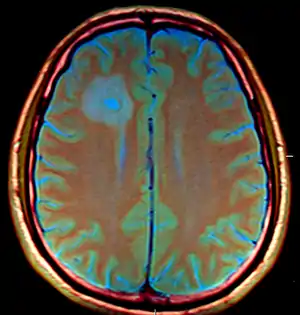

| Brain abscess in a person with a CSF shunt.[1] | |

The diagnosis is established by a computed tomography (CT) (with contrast) examination. At the initial phase of the inflammation (which is referred to as cerebritis), the immature lesion does not have a capsule and it may be difficult to distinguish it from other space-occupying lesions or infarcts of the brain. Within 4–5 days the inflammation and the concomitant dead brain tissue are surrounded with a capsule, which gives the lesion the famous ring-enhancing lesion appearance on CT examination with contrast (since intravenously applied contrast material can not pass through the capsule, it is collected around the lesion and looks as a ring surrounding the relatively dark lesion). Lumbar puncture procedure, which is performed in many infectious disorders of the central nervous system is contraindicated in this condition (as it is in all space-occupying lesions of the brain) because removing a certain portion of the cerebrospinal fluid may alter the concrete intracranial pressure balances and causes the brain tissue to move across structures within the skull (brain herniation).

Ring enhancement may also be observed in cerebral hemorrhages (bleeding) and some brain tumors. However, in the presence of the rapidly progressive course with fever, focal neurologic findings (hemiparesis, aphasia etc.) and signs of increased intracranial pressure, the most likely diagnosis should be the brain abscess.